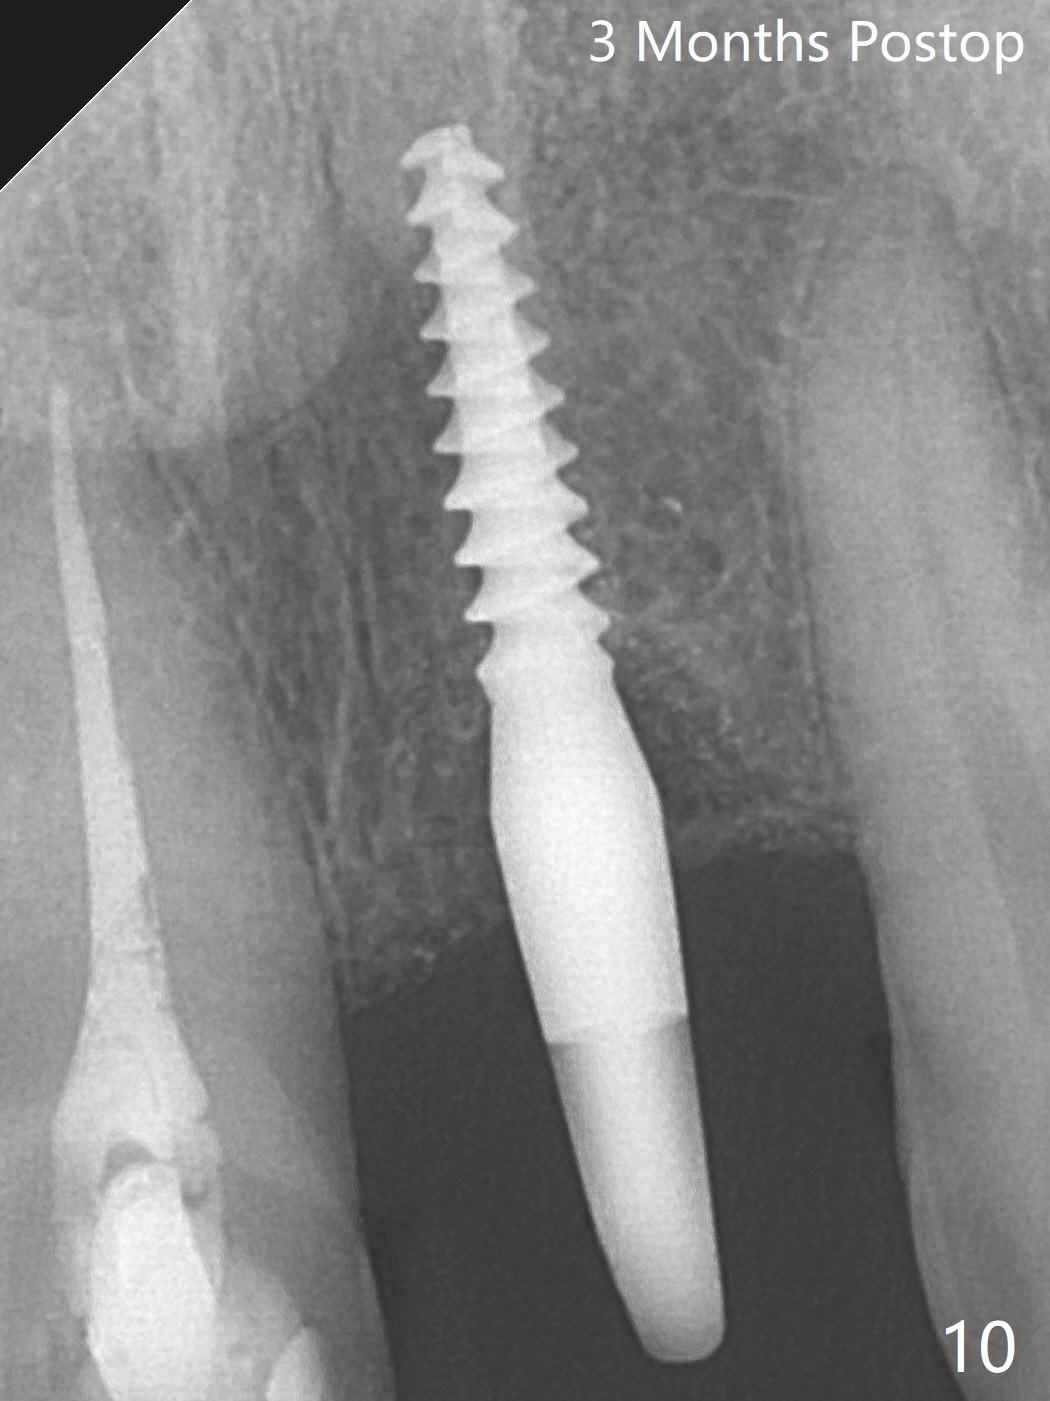

Three months postop there is no gross bone loss around the implant (Fig.10).